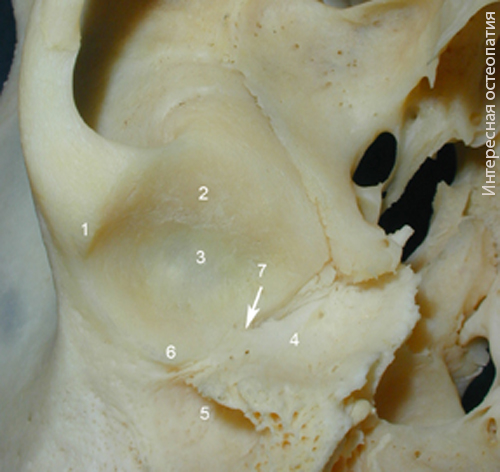

Рис. Основание правой височной кости. 1 — скуловой отросток височной кости, 2 — височный выступ, 3 — нижнечелюстная ямка, 4 — барабанная часть височной кости, 5 — наружный слуховой проход, 6 — задний суставной бугорок, 7 — барабанно-чешуйчатая щель.